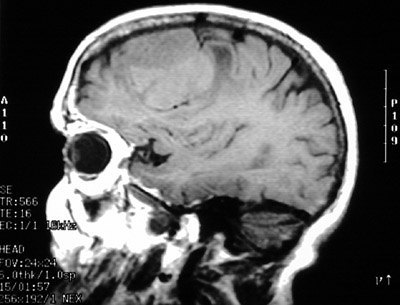

This MRI scan in axial view above and sagittal view below demonstrates a meningioma in the parasagittal region over frontal lobe.